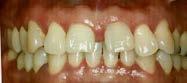

En los estudios intraorales de inicio en las fotografías se muestra en la de frente el diastema anterior, con la línea media dental superior e inferior no coincidentes, la mordida profun da anterior (Figura 2), en la lateral derecha clase l molar y canina bila teral (Figura 3), el apiñamiento leve superior e inferior y la forma de las arcadas.

En las fotografías intraorales finales se ve la corrección del apiñamiento maxilar y mandibular, la forma de las arcadas es ovalada, se consiguió guía de desoclusión canina derecha e izquierda, la mordida profunda

anterior (Figura 10), la estabilidad oclusal, la máxima intercuspidación, el paralelismo radicular y oclusión funcional, el cierre de diastema ante rior, las líneas medias superior-infe rior coincidieron ambas con la facial.